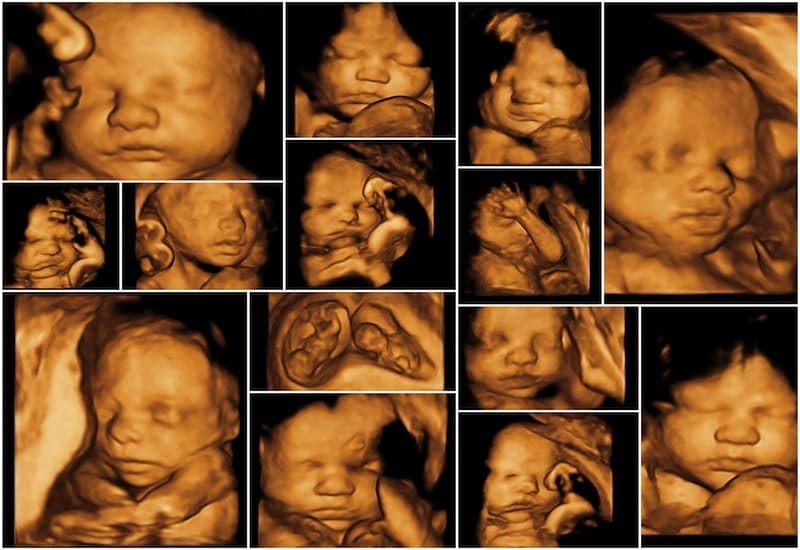

Siêu âm thai 5D được ưa chuộng bởi vì đây là công nghệ siêu âm hiện đại nhất hiện nay, vừa đáp ứng nhu cầu chẩn đoán y khoa chính xác vừa mang lại trải nghiệm cảm xúc đặc biệt cho gia đình. Với độ phân giải cao và khả năng mô phỏng sống động, thai nhi được tái hiện gần như chân thực trong bụng mẹ, từ khuôn mặt, cử động cho đến những biểu cảm nhỏ. Bên cạnh đó, siêu âm 5D còn giúp bác sĩ dễ dàng phát hiện các bất thường và theo dõi sự phát triển của bé kịp thời. Chính sự kết hợp giữa yếu tố chuyên môn và giá trị tinh thần này đã khiến siêu âm 5D ngày càng được nhiều mẹ bầu tin chọn.

- Hình ảnh rõ nét, chi tiết, giúp bố mẹ quan sát con như ngoài đời thực.

- Hình ảnh rõ nét, chân thực: Công nghệ 5D cho phép quan sát chi tiết khuôn mặt, tay, chân, biểu cảm và cử động của thai nhi, giống như nhìn thấy trực tiếp em bé ngoài đời thực.

Bamboo Care ứng dụng công nghệ siêu âm 5D hiện đại, mang đến hình ảnh thai nhi sắc nét và sống động. Mẹ bầu có thể dễ dàng quan sát khuôn mặt, tay chân, thậm chí cả biểu cảm nhỏ của bé ngay trong bụng mẹ. Đây không chỉ là bước kiểm tra y khoa mà còn là trải nghiệm đầy cảm xúc cho gia đình. Nhờ chất lượng hình ảnh vượt trội, nhiều mẹ đã tin tưởng lựa chọn dịch vụ siêu âm thai 5D tại Vinh tại Bamboo Care để lưu giữ những khoảnh khắc đáng nhớ này.